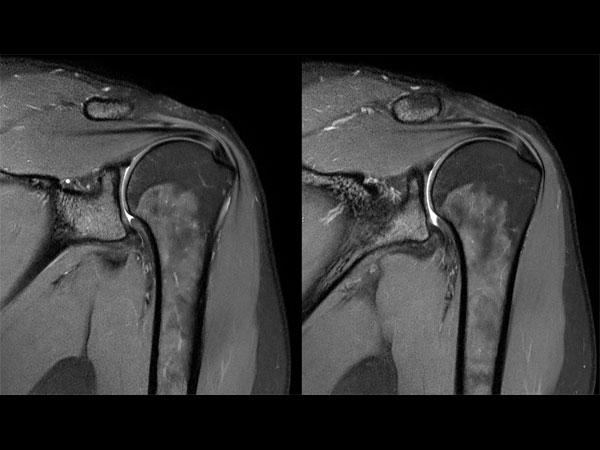

Shoulder imaging with dS Flex coil

Used Solution

• System

• Coil